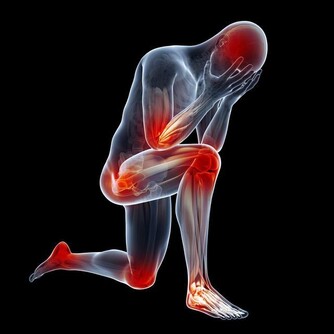

統計數據表明,我國每年都有超過50萬人死於心臟病,平均每分鐘都有1人死於心臟猝死。這類疾病一旦發作,留給醫護人員的搶救時間非常短。如果能儘早發現問題,及時接受治療,那麼可以明顯降低疾病突發的風險。心臟在出現問題時,人體通常會發出以下4種警告信號: